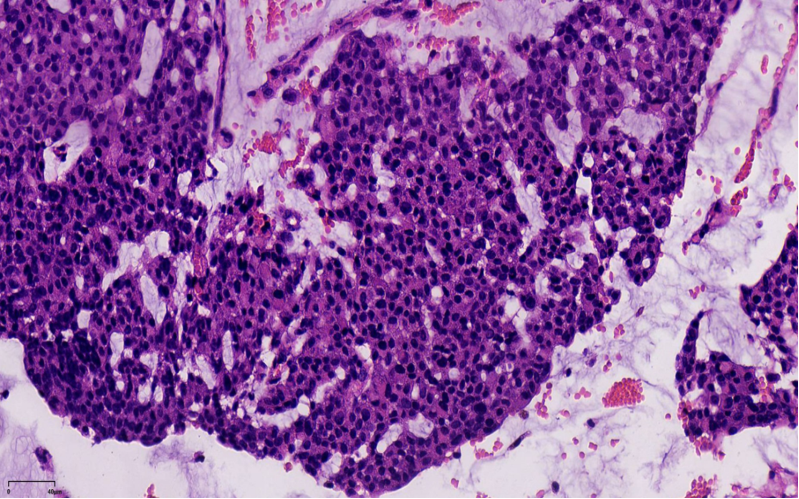

浸润癌两种浸润方式

1、浸润性实性乳头状癌:保留实性乳头状结构,体积大的团巢,轮廓不规则,间质促纤维反应,肌上皮缺失,原位SPC背景

2、实性乳头状癌伴浸润:轮廓圆滑的结节,伴有浸润性成分,包括粘液癌,NET,浸润性癌(NST)

SPC+富于细胞的黏液癌

浸润性SPC

当在原位SPC的背景上,部分原位SPC轮廓变得不规则,或呈地图、锯齿状,并出现促纤维反应,或浸润脂肪,可称为原位SPC伴浸润(毁损性浸润),这时需按浸润癌处理。